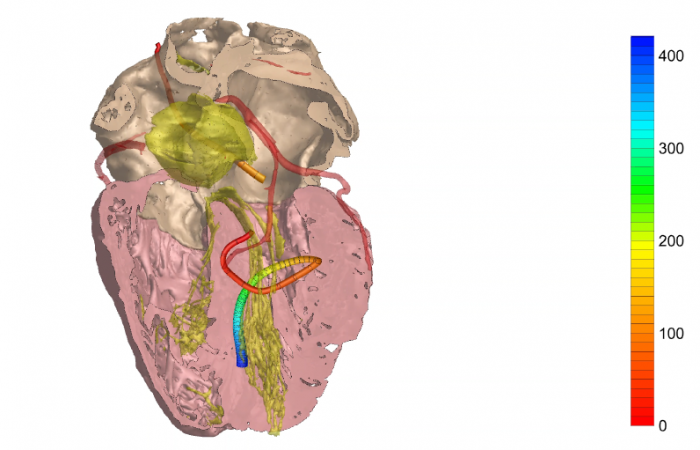

Pracownia Funkcjonalnego i Wirtualnego Medycznego Obrazowania 3D (Pracownia 3D-FM) funkcjonuje w strukturze Zakładu Diagnostyki Obrazowej Szpitala Uniwersyteckiego w Krakowie pod kierownictwem Prof. dr hab. Tadeusza Popieli. Jej celem jest opracowanie i wdrożenie innowacyjnych metod przetwarzania oraz analizy sygnałów i obrazów medycznych, w tym wykorzystanie technologii rzeczywistości wirtualnej oraz metod obrazowania funkcjonalnego. Rozwiązania te wspierają przedoperacyjne planowanie, monitorowanie procedur medycznych oraz wzbogacają proces diagnostyczny o nowe formy wizualizacji danych medycznych.

Zakres działalności

Pracownia 3D-FM zajmuje się m.in. następującymi obszarami:

- Tworzeniem modeli 3D do celów przedoperacyjnego planowania oraz wizualizacji diagnostycznej.

- Obrazowanie Medyczne 3D

- Segmentacja i analiza danych DICOM

- Rekonstrukcja danych medycznych

- Technologie immersyjne (mieszana, rozszerzona i wirtualna rzeczywistość)

- Obrazowanie funkcjonalne

- Elektrokardiograficzne obrazowanie 3D (ECGI)

- Modelowanie fizjologiczne

Pracownia Funkcjonalnego i Wirtualnego Medycznego Obrazowania 3D łączy nowoczesne technologie z praktycznym zastosowaniem w diagnostyce i terapii. Dzięki interdyscyplinarnej współpracy oraz zaawansowanym narzędziom badawczym dążymy do podnoszenia standardów opieki medycznej w Szpitalu Uniwersyteckim w Krakowie.